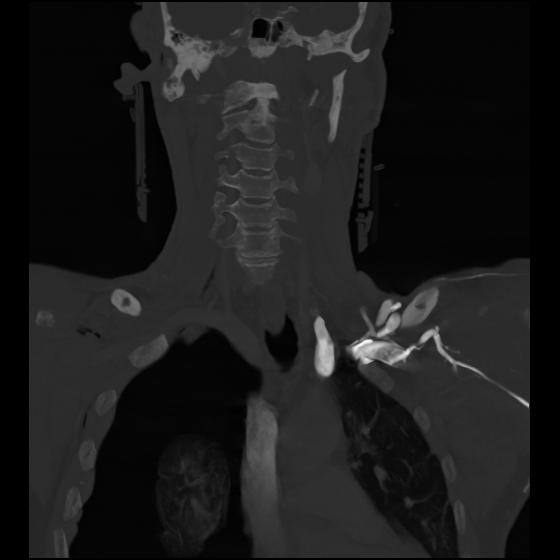

23 ANGIO,CE,Cor-MIP,5.000,ANGIO,Cor-MIP,